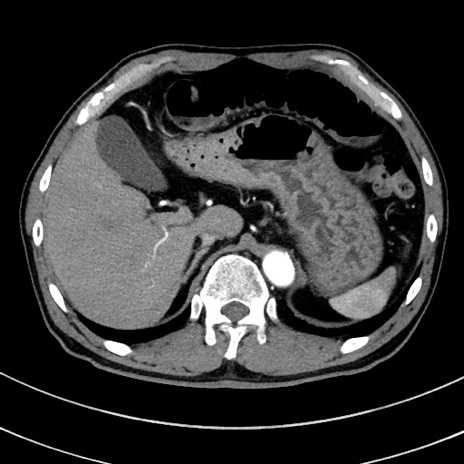

症例8(横断像)

【症例】 60歳代男性

【主訴】 黒色吐物

【現病歴】 4日前から嘔気自覚、2日前の朝食後にも嘔気あり、自分で手で嘔吐反射起こし嘔吐したところ血が混ざっていたため受診。

【既往歴】 5年前汎発性腹膜炎を伴う急性虫垂炎で手術、高血圧、前立腺肥大症、高脂血症

【身体所見】 腹部正中に手術癩痕あり 腹部平坦・軟圧痛なし膨満感あり

【データ】WBC 8400、CRP 4.54